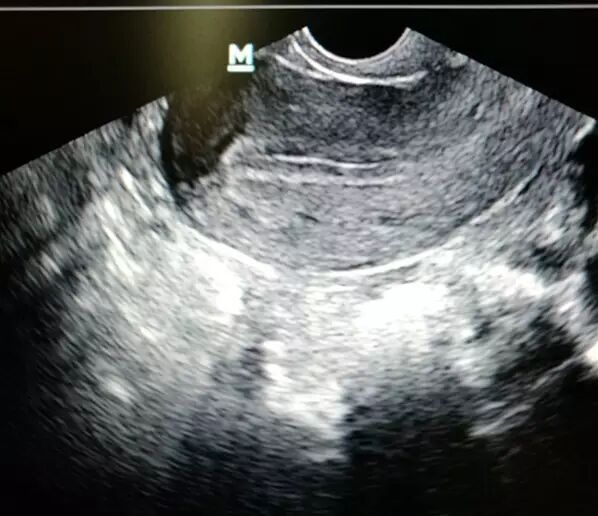

3 . 肥胖与卵子

大量辅助生殖治疗周期数据显示肥胖患者治疗周期所需促性腺激素剂量增加即便是有相同数目的生长期卵泡肥胖者获卵数及成熟卵子数减少,提示肥胖可能是造成卵子成熟障碍的相对独立因素。行体外受精助孕治疗肥胖患者卵泡液内人绒毛膜促性腺激素水平较对照组显著降低也可能是导致卵子成熟率降低的原因。试管周期的卵子受精率是评估卵子质量的另一重要指标肥胖患者卵子受精率显著下降已经多方证实。也有学者认为肥胖妇女早期流产也可能是卵子质量降低所致。小鼠试验发现肥胖小鼠卵子发育能力降低受精后胚胎发育延缓直至囊胚期胚胎的发育潜能受损影响囊胚植入过程降低种植率。